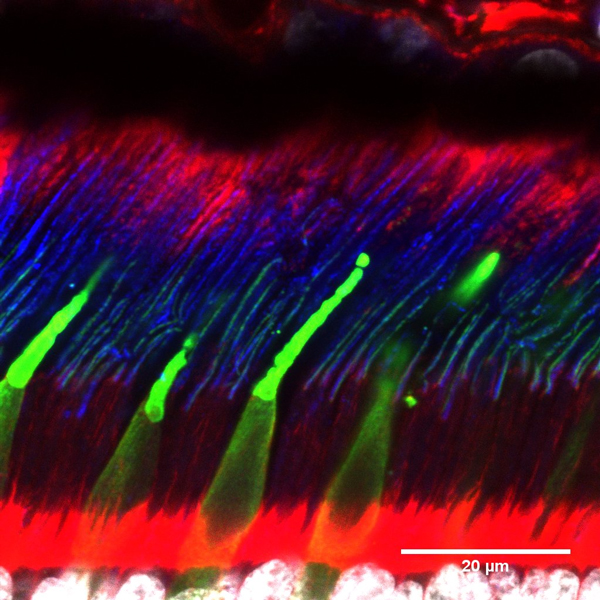

Maya-Vetencourt, J. F. et al. A fully organic retinal prosthesis restores vision in a rat model of degenerative blindness. Nat. Mater. 16 681-689 (2017).

Ghezzi, D. et al. A polymer optoelectronic interface restores light sensitivity in blind rat retinas. Nat. Photonics 7, 400–406 (2013).

Dr Serge Picaud, PhD is Research Director (INSERM, orcid.org/0000-0002-0548- 5145). He is the head of the Department of Visual Information processing at the Vision Institute. His team is investigating visual function in normal and pathological conditions to understand our vision, develop models of retinal pathology and propose new therapeutic treatments. In the last 10 years, the team has been involved in developing strategies for restoring vision from retinal implants to optogenetic therapies. These strategies are first examined on in vitro models such as retinal explants from rodent, primate or even post-mortem human retina and then validated on living rodents or non-human primates. These validations involve functional in vitro measurements from patch-clamp, multielectrode array (MEA) recording or calcium imaging and in vivo measurement like MEA recording as well as ultrafast ultrasound imaging providing greater resolution than MRI. The team has also access to phenotyping platforms on both rodents and non-human primates including the following technologies (eye fundus examination, Scanning laser ophthalmoscope (SLO), Optical coherence tomography (OCT), electroretinogram and visual evoked potential recording). Finally, restoration of vision is demonstrated by behavioural evaluations such as saccades in non-human primates. These preclinical studies have enabled the team to contribute to several products entering into clinical trials like retinal prostheses with Pixium Vision (NCT03333954) and optogenetic therapy with Gensight biologics (NCT03326336).

Trouillet A, Dubus E, Dégardin J, Estivalet A, Ivkovic I, Godefroy D, García-Ayuso D, Simonutti M, Sahly I, Sahel JA, El-Amraoui A, Petit C, Picaud S. Cone degeneration is triggered by the absence of USH1 proteins but prevented by antioxidant treatments. Sci Rep. (2018) 8:1968. doi: 10.1038/s41598-018-20171-0.

Busskamp V, Duebel J, Balya D, Fradot M, Viney TJ, Siegert S, Groner AC, Cabuy E, Forster V, Seeliger M, Biel M, Humphries P, Paques M, Mohand-Said S, Trono D, Deisseroth K, Sahel JA, Picaud S, Roska B. Genetic Reactivation of Cone Photoreceptors Restores Visual Responses in Retinitis pigmentosa. Science (2010) 329: 413-7.